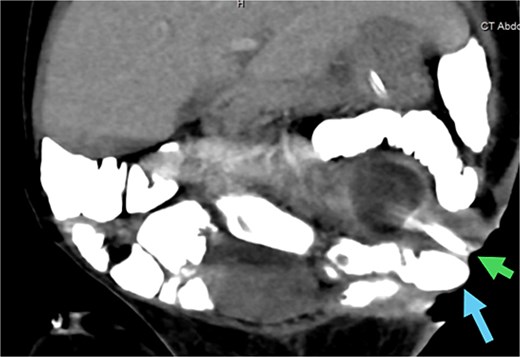

An abdominal CT scan with oral contrast revealed two ECFs: the first connected to the small bowel (Fig. 6, green arrow, corresponding to fistula number 1 in Fig. 5), and the second connected to the proximal sigmoid colon (Fig. 6, blue arrow, corresponding to fistula number 2 in Fig. 5). Furthermore, an enteroenteric fistula between the ileum and rectosigmoidal junction was noted (Fig. 7, red arrow).

CT abdomen with oral contrast showing two enterocutaneous fistulas. Green arrow: fistula connected to the small bowel. Blue arrow: fistula connected to the proximal sigmoid colon.